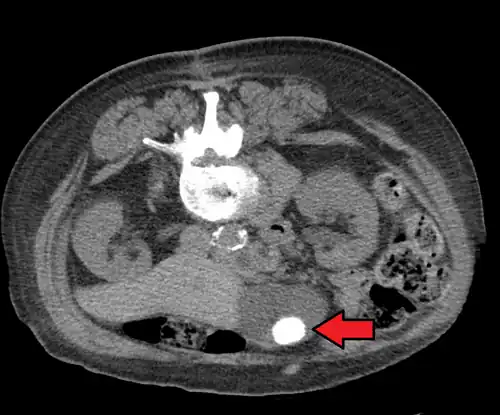

Large gallstone as seen on CT -

Choledocholithiasis

Choledocholithiasis refers to a gallstone obstructing the common bile duct.[20] Patients typically experience right upper quadrant pain, back pain, jaundice (or yellowing of the skin), decreased appetite, nausea, vomiting, and fever.[13][20] However, choledocholithiasis, just like gallstones, can also be asymptomatic.[14][21] If the patient has symptoms, the physical exam is similar to that of acute cholecystitis.[20] Laboratory studies show an increase in direct (conjugated) bilirubin, gamma-glutamyl transpeptidase (GGT), and alkaline phosphatase. AST and ALT can be elevated or normal.[14][15][21]